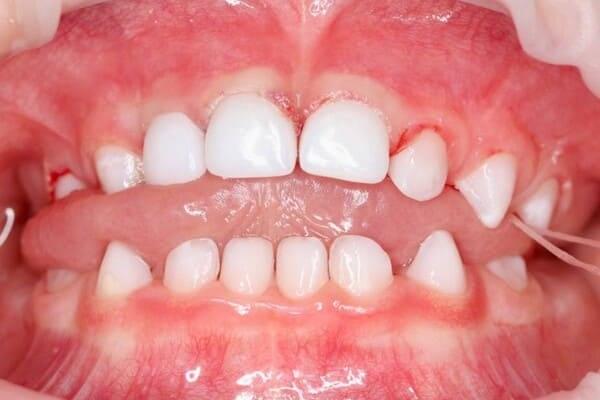

Дівчинка 2 років, але зуби вже мають глибокі ураження із залученням у запальний процес пульпи (“нерва”) зуба. На жаль, так трапляється і зволікати в такому випадку не можна. Було проведено лікування в умовах анестезіологічного забезпечення під контролем досвідченої анестезіологічної команди. Передні зубчики відновлено естетичними коронками, на жувальних зубчиках проведена герметизація фісур, а один вже має глибоке ураження карієсом, тому теж покритий коронкою. Одразу після лікування ясна можуть виглядати дещо травмованими, але за кілька днів вони повністю відновляться.